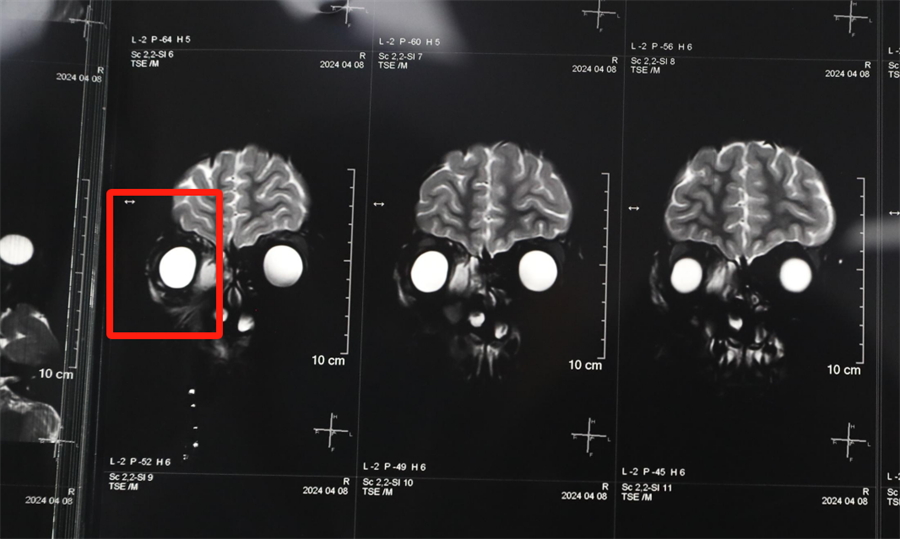

经眼科、耳鼻喉科联合会诊,医生发现孩子是因为患了急性鼻窦炎,导致右眼急性细菌感染,确诊为“右侧眶蜂窝织炎、眶内脓肿”。考虑到此病进展较快,可能导致视力下降甚至失明,耳鼻喉科立即将患儿收治入院。静脉输液、对症支持治疗、密切监测视力变化,一切有条不紊。入院第2天,孩子自觉右眼视力下降明显,眼科紧急会诊发现,其右眼视力从患病前的1.0下降到0.4。

北京儿童医院常驻专家、a片网站 副院长杨小健决定立即手术治疗引流眶内脓液,并组织多学科联合会诊。考虑到患儿年龄较小,杨小健副院长决定采取内镜经鼻腔手术引流脓液,这种手术方式创伤小、恢复快、效果确切,而且避免了外切口瘢痕,不需要反复进行局部消毒换药。但是孩子鼻腔解剖结构本身就狭窄,而且处于急性感染期,术中出血风险较大,手术难度较高,对麻醉技术也有着很高的要求。

孩子左侧鼻腔3年来没有通气,鼻腔的发育受到了严重影响,甚至部分结构出现了一定程度的萎缩,并患有严重的鼻窦炎。杨小健副院长认真分析了孩子的病情,认为应该尽快手术治疗。